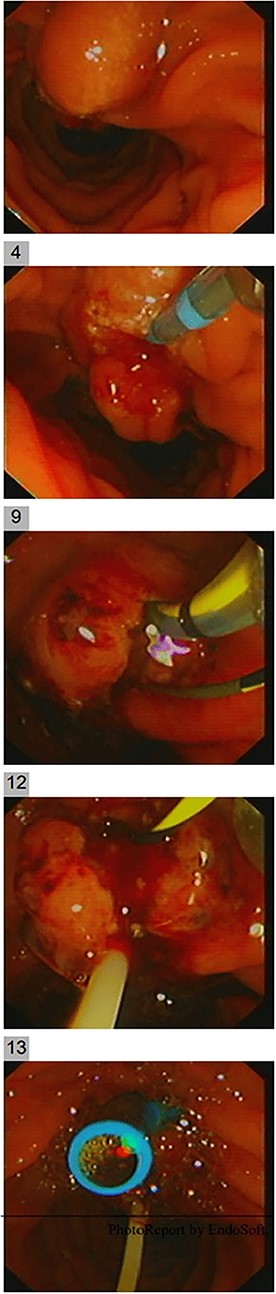

Endoscopic ultrasound (EUS) was carried out to delineate the anatomy and the location of the ampulla of vater (AOV) and showed an abnormally located AOV in the distal duodenum (D4) with dilated CBD. Endoscopic retrograde cholangiopancreatography [ERCP] was performed in the same setting with difficulties in cannulating the ectopic AOV that was associated with mucosal abnormality. After multiple trials, the cannulated pancreaticogram was unremarkable (Fig. 2). The double-wire technique is used to cannulate CBD. Cholangiogram revealed a short distal filling defect suspicious for stones. Several balloon sweeps were done, but no stones were retrieved. Cytology brushing and fluoroscopically guided intraductal biopsy were done. Also, mucosal ampullary biopsies were taken as well. Then, a CBD stent was inserted. The cytology was inconclusive. However, the ampullary biopsy revealed high-grade dysplasia, and invasive carcinoma could not be excluded. Therefore, she was suspected to have ampullary malignancy.